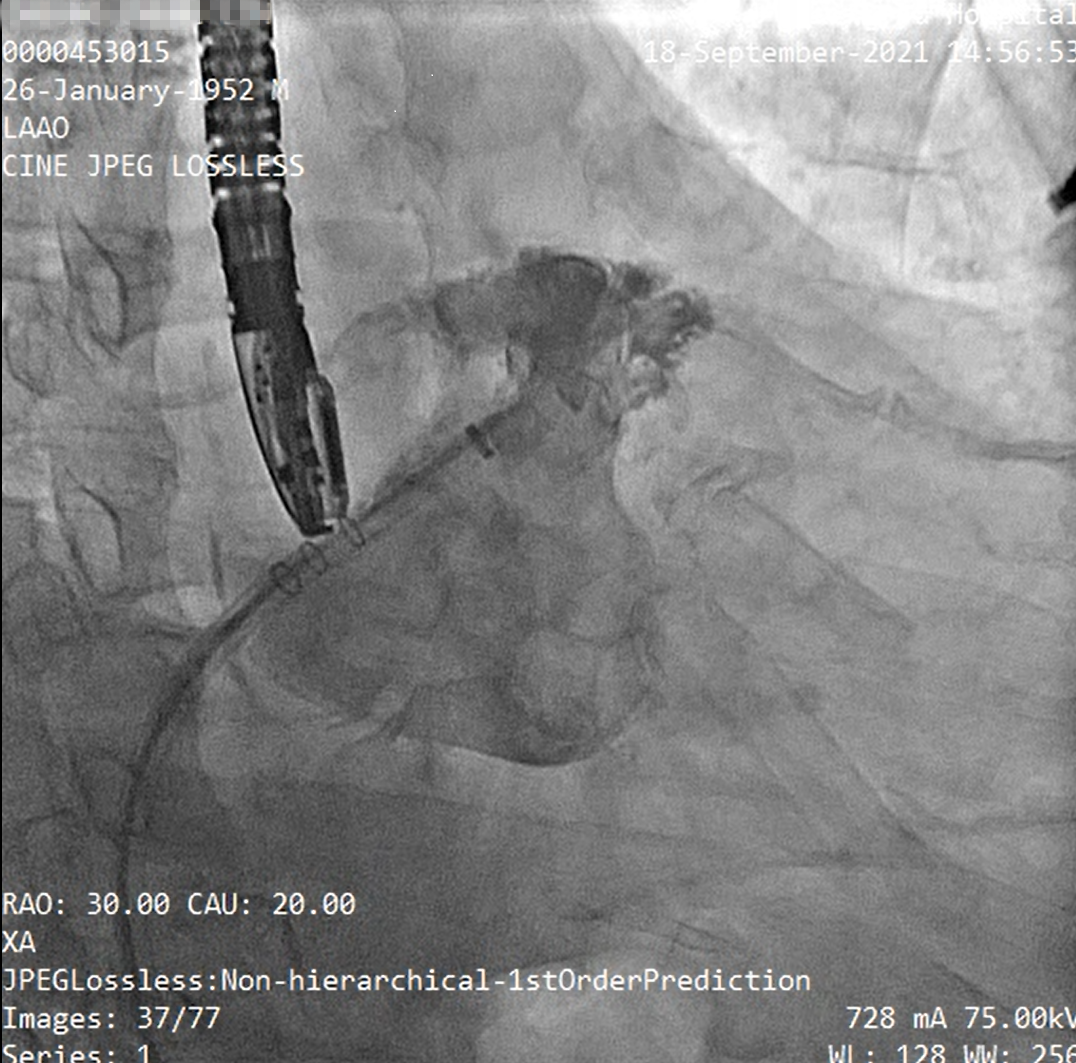

食道超声及左心耳造影

释放左心耳封堵器呈〝FLX BALL〞

经造影及食道超声检查后释放WATCHMAN FLX左心耳封堵器